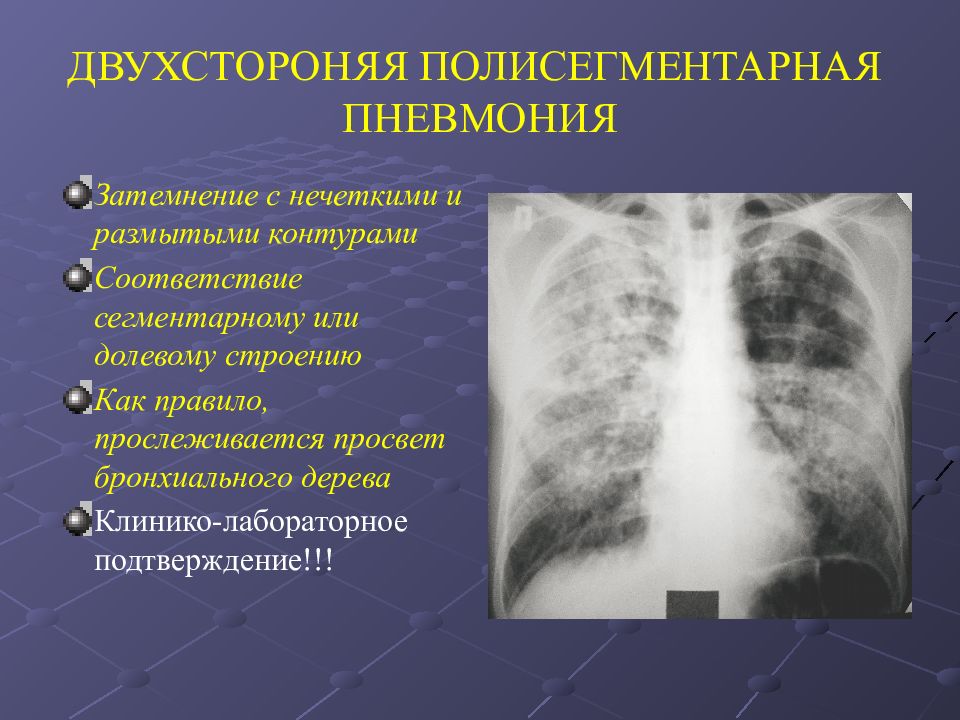

Рентгеновские снимки при пневмоцистной пневмонии